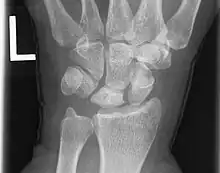

Sur les formes plus évoluées, la radiographie permet le diagnostic de la maladie. Les anomalies radiographiques sont regroupées dans la classification de Lichtman[6] qui reflète l'évolution de la maladie :

- Stade I : radiographie normale.

- Stade II : augmentation de la densité du lunatum.

- Stade IIIa : aplatissement du lunatum (de profil confirmé par une anomalie de l'index de Stahl).

- Stade IIIb : aplatissement du lunatum et bascule palmaire du scaphoïde (de profil confirmé par une anomalie de l'angle radio-scaphoïdien).

- Stade IIIc : Fracture du lunatum.

- Stade IV : arthrose intra-carpienne ou radio-carpienne (Kienböck's Disease Advanced Collapse : KDAC) .